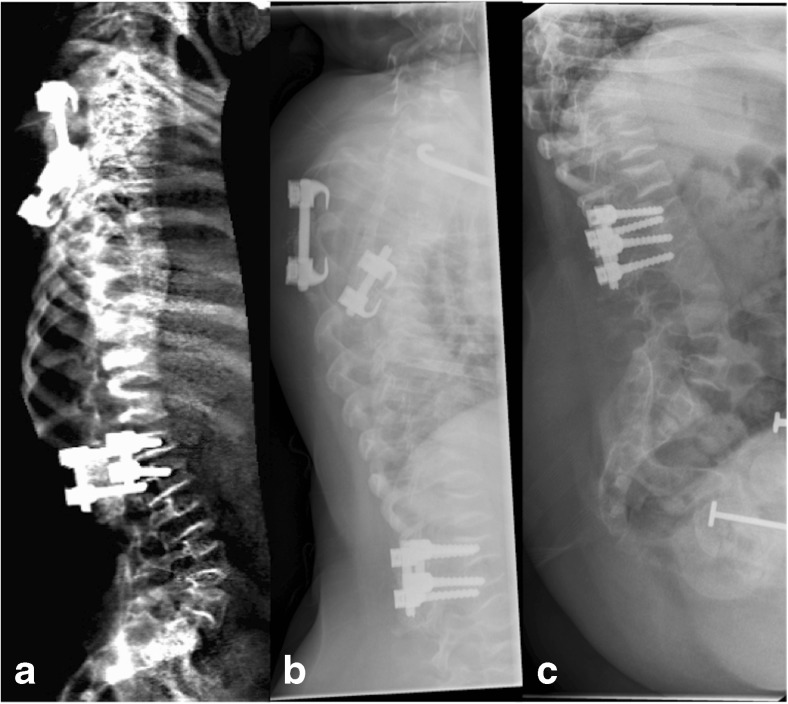

Tuttavia, la MRX presenta limiti tecnici non trascurabili. La divergenza del fascio radiogeno può causare distorsioni geometriche e il fenomeno della parallasse, rendendo difficile la precisa individuazione dei bordi vertebrali, specialmente in presenza di scoliosi. Inoltre, richiede che il paziente sia posizionato con estrema cura per garantire che i corpi vertebrali siano perfettamente paralleli al piano sensibile, onde evitare la proiezione di “doppi contorni” delle limitanti somatiche che invaliderebbero la misurazione.

- considerazioni su scoliosi e obesità: la presenza di grave scoliosi o obesità marcata rappresenta una limitazione tecnica significativa. In questi casi, la qualità dell’immagine VFA può degradarsi al punto da non permettere una misurazione accurata, rendendo preferibile la radiologia convenzionale o la CT.

L’uso di sistemi basati sull’IA per prevedere la proiezione sagittale partendo dalla coronale permette di quantificare le rotazioni vertebrali e le deformazioni scoliotiche con una precisione simile alla risonanza magnetica, ma con una frazione del costo e del tempo.19